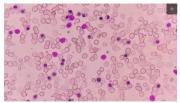

Thalassemia merupakan penyakit darah akibat kelainan pembentukan hemoglobin (Hb). Hemoglobin adalah komponen darah yang bertugas mengikat oksigen dan menjadi “kurir” yang mengantar oksigen untuk jaringan tubuh lain melakukan metabolisme dan beraktivitas. Hemoglobin tidak mampu mempertahankan bentuknya dan mudah pecah, sehingga tidak mampu mengikat dan mengantarkan oksigen ke jaringan yang membutuhkan.

Gejala-gejala yang sering muncul seperti kulit kuning dan pucat akibat kurangnya kadar hemoglobin (anemia) dan perut yang membesar juga bisa terjadi. Selain itu, gejala anemia lainnya seperti badan lemas, berdebar, yang jika berlangsung lama dapat mengganggu perkembangan dan pertumbuhan anak. Meskipun begitu, diagnosis thalassemia baru bisa ditegakkan dengan pemeriksaaan darah seperti kadar hemoglobin yang menandakan anemia, total zat besi dalam tubuh, dan lain-lain.

Pada thalassemia, kadar hemoglobin yang rendah membuat tugasnya sebagai kurir oksigen tak berfungsi dengan baik, sehingga oksigen berkurang di berbagai jaringan tubuh. Tentu saja ini berbahaya jika tidak ditangani. Karena, secara keseluruhan tubuh gagal melakukan aktivitas dan metabolismenya.